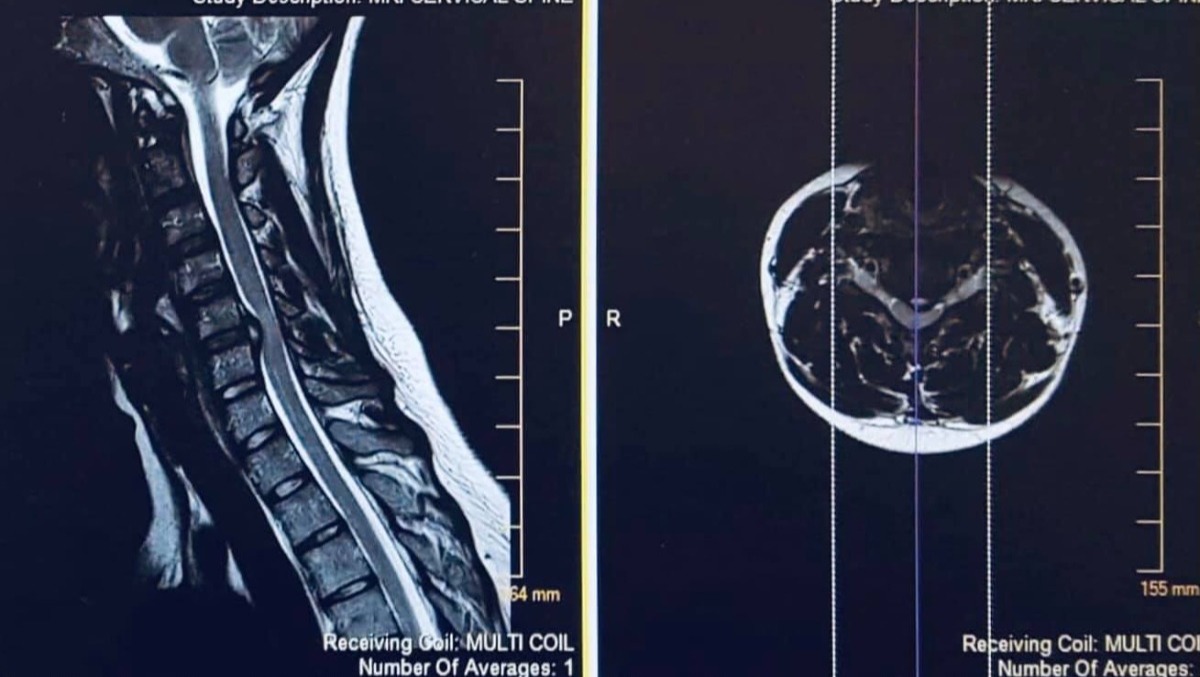

Fast forward to early 2019. After going round and round with doctors for over a year about some excruciating pain in her neck and back and radiating to other parts of her body, she finally got an MRI which showed she had a disc in between C5 and C6 that was flattening her spinal cord. The doctor suspected it could potentially be early stage Myelomalacia in April of 2019. Myelomalacia is a serious injury which requires a much longer time to accurately diagnose, but even suspecting that is a serious issue. Because of the severity of the injury, she was scheduled to meet with a neurosurgeon to address the issue ASAP. The neurosurgeon advised she had gone from moderate to severe stenosis and flattening of her spinal cord. Her disc extrusion had gotten worse just in the weeks between the MRIs and the doctor told her he was surprised she was even alive.